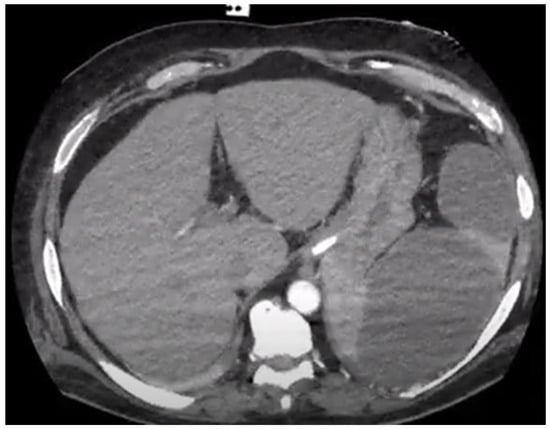

- Vancauwenberghe, T.; Snoeckx, A.; Vanbeckevoort, D.; Dymarkowski, S.; Vanhoenacker, F.M. Imaging of the spleen: What the clinician needs to know. Singap. Med. J. 2015, 56, 133–144. [Google Scholar] [CrossRef] [PubMed]

- Peddu, P.; Shah, M.; Sidhu, P.S. Splenic abnormalities: A comparative review of ultrasound, microbubble-enhanced ultrasound and computed tomography. Clin. Radiol. 2004, 59, 777–792. [Google Scholar] [CrossRef]

- Colen, T.W.; Gunn, M.; Cook, E.; Dubinsky, T. Radiologic manifestations of extra-cardiac complications of infective endocarditis. Eur. Radiol. 2008, 18, 2433–2445. [Google Scholar] [CrossRef] [PubMed]